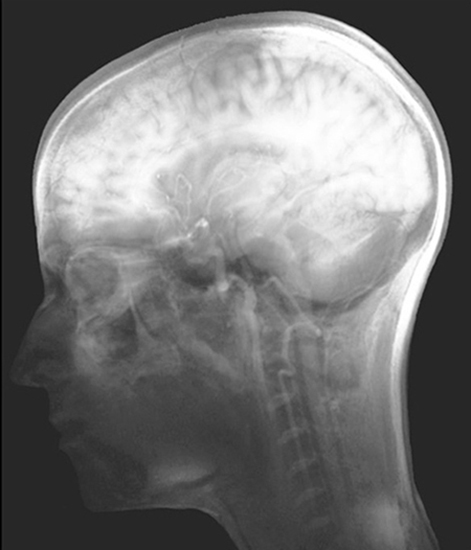

seeing ourselves

MuseCPMI, 580 Eight Avenue, New York NY, 10018 (2012)

Curated by Koan Jeff Baysa, M.D. and Caitlin Hardy, M.D.

Artist: Suzanne Anker, Deborah Aschheim, Stephen Auger, Christophe Berdaguer and Marie Pejus with Christophe Laudamiel and Christoph Hornetz, Stefani Bardin and Toby Heys, Jonathan Beer, Nancy Burson, Naomi Campbell, caraballo-farman, Joyce Cutler-Shaw, Scott Draves, Simon Drouin, Greg Dunn, Laura Ferguson, Angela Freiberger, Pablo Garcia, Peter Garfield, Sarah Elise Hall, Hugh Hayden, Pinkney Herbert, Joann Hoffmann, Nene Humphrey, Elizabeth Jameson, Sophie Kahn, Andrea Kantrowitz, Mark Kessell, Adrienne Klein, Bodo Korsig, Lilla LoCurto and Bill Outcault, Marcos Lutyens, Kate MacDowell, Michael Madore, Daniel Margulies and Chris Sharp, Patrick Martinez, Saul Melman, Igor Molochevski, Gayil Nalls, Natsu, Francesca Samsel, Anne Senstad, Jason Snyder, Max Steiner, Satre Stuelke, Visual MD, Claire Watkins, David Webster, Heron Werner MD with Professors Jorge Lopes dos Santos and Ricardo Fontes, Graham Wiggins, Virgil Wong with Jessica Lacson and Akshay Kapur.